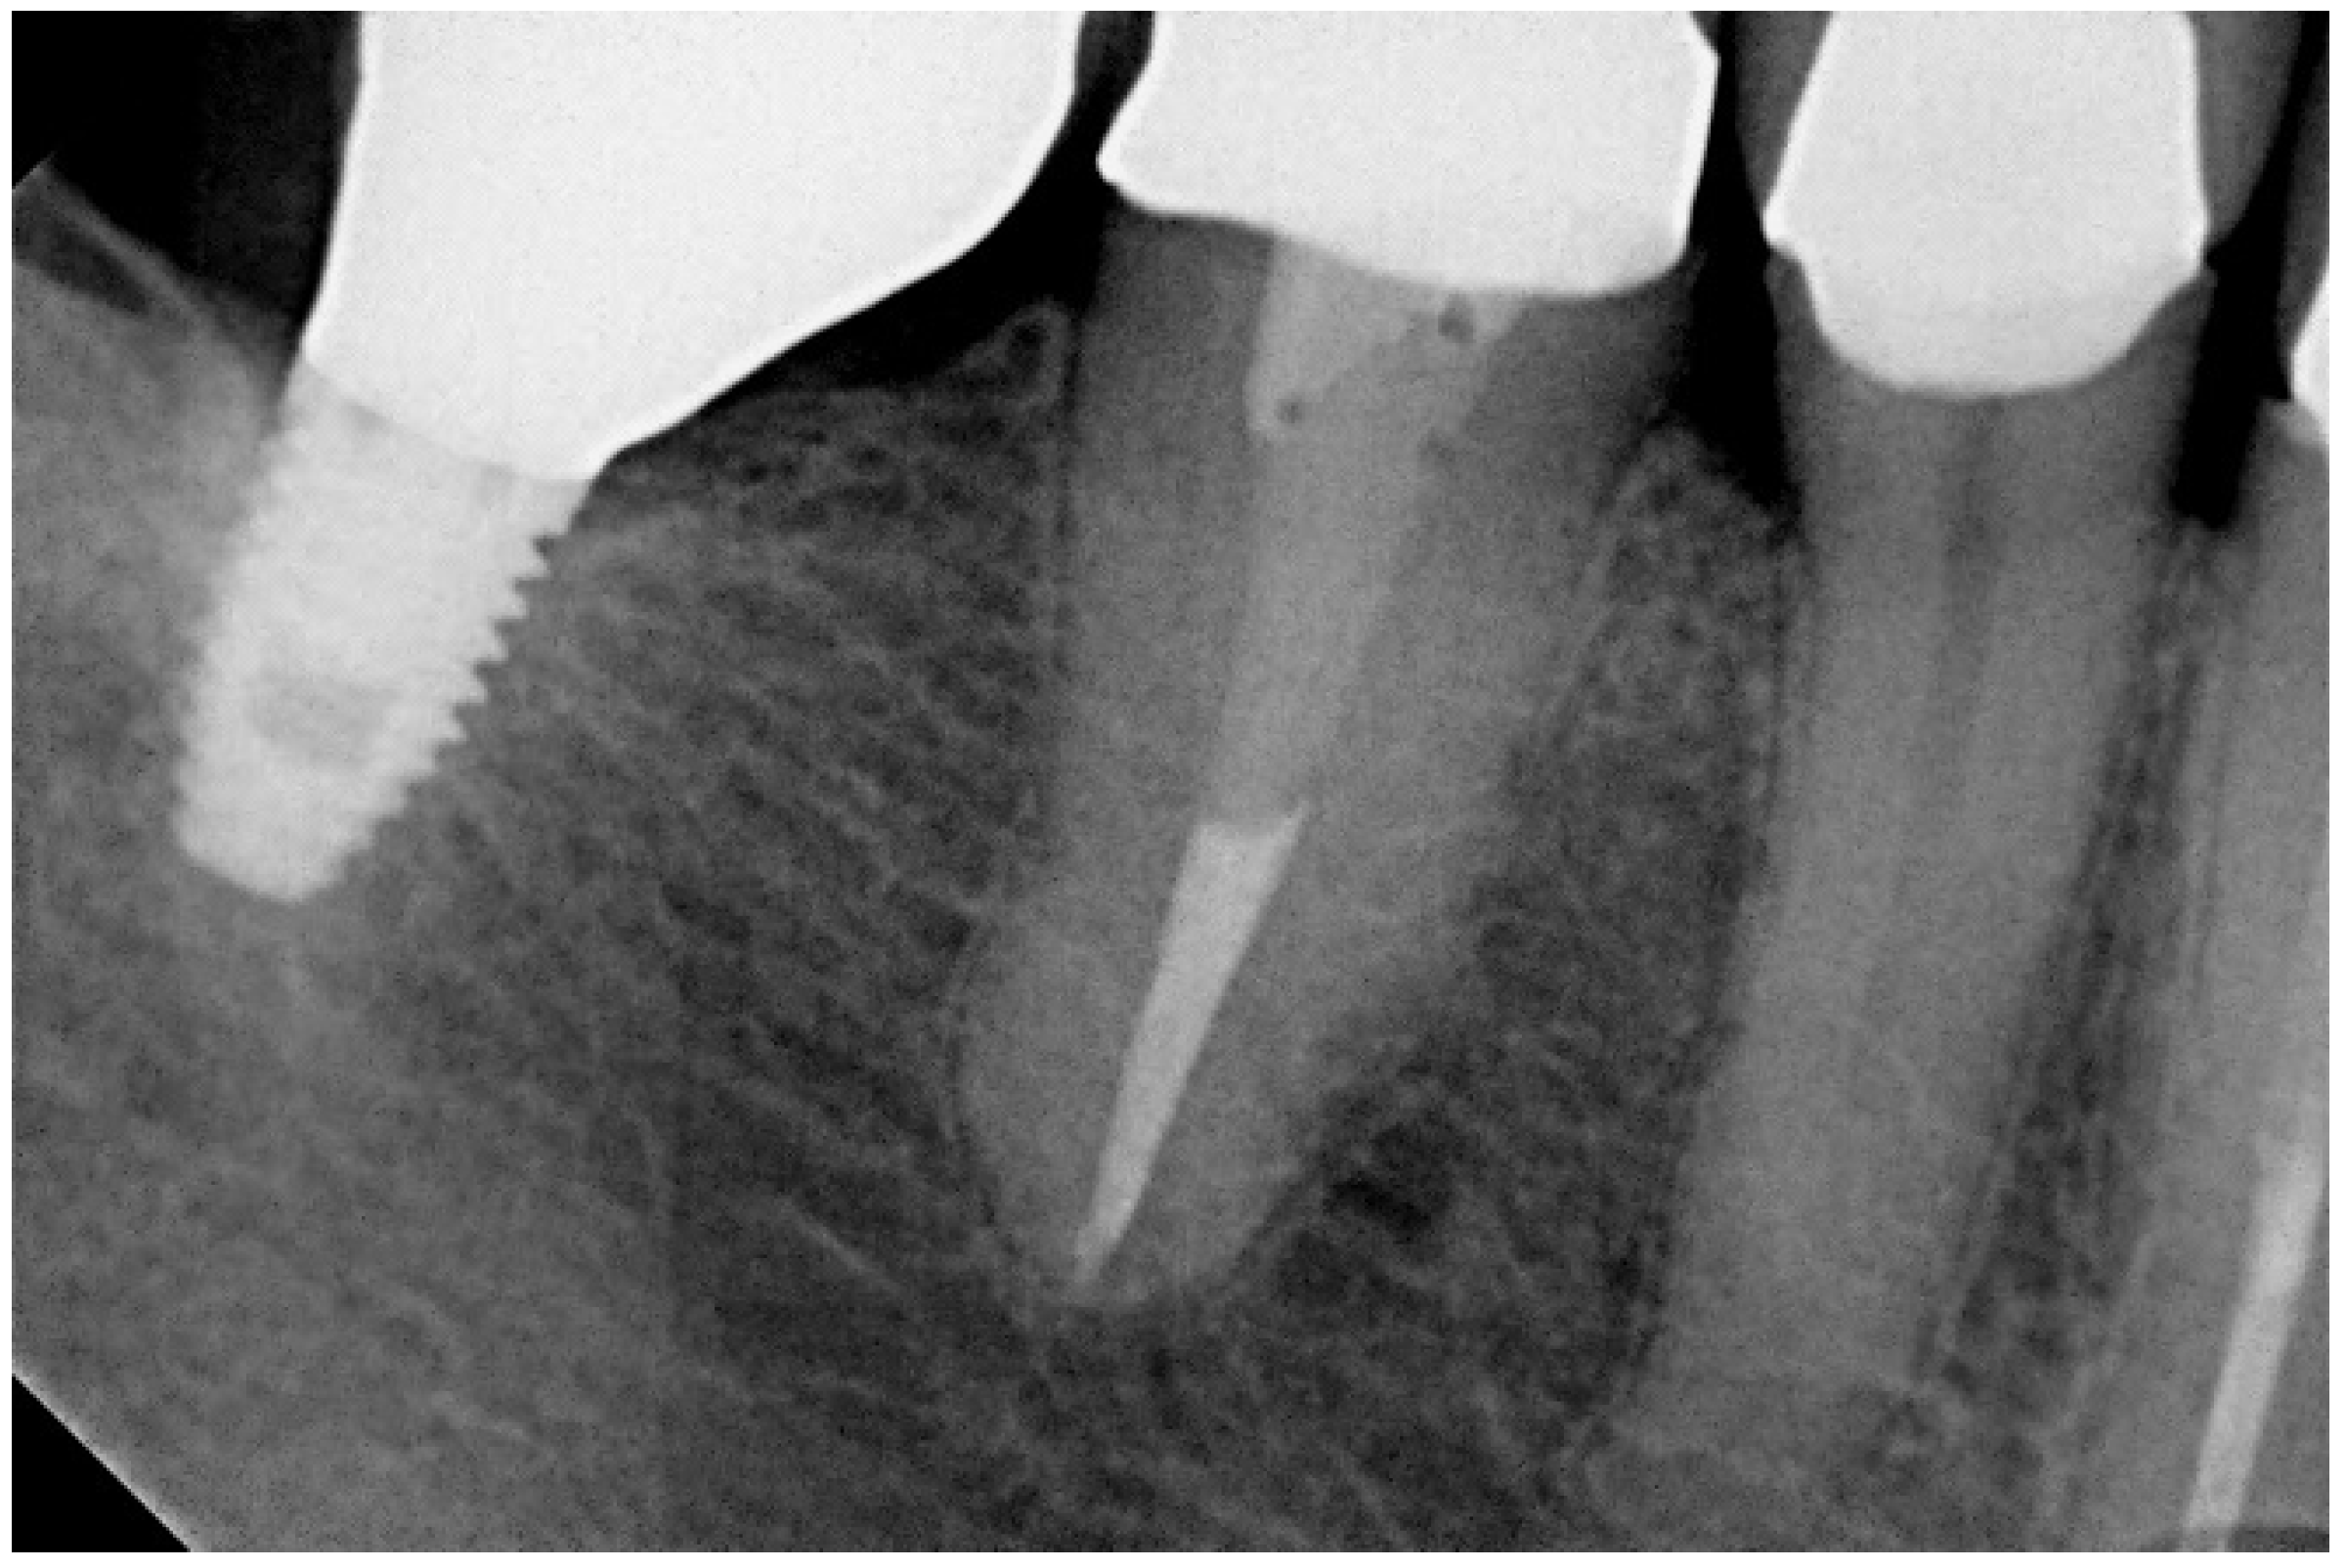

Periapical radiographs were taken using the parallel technique with a film holder (Super-bite, Hawe-Neos, Bioggio, Switzerland) and an aiming device on the day of implant insertion and 5 years post-surgery. An outcome assessor examined all periapical radiographs. Each periapical radiograph was scanned at 300 dpi with a scanner (HP Scanjet 4890, HP Portugal, Paço de Arcos, Portugal), and the marginal bone level was measured with an image analysis software (Image J version 1.40 g for Windows, National Institutes of Health, Stapleton, NY, USA). The reference point for the reading was the implant platform (the horizontal interface between the implant and the abutment), and marginal bone loss was defined as the difference in the marginal bone level relative to the bone level at the time of surgery as seen on the periapical radiograph. The radiographs were accepted or rejected for evaluation based on the clarity of the implant threads; a clear thread guaranteed both sharpness and the orthogonal direction of the radiographic beam towards the implant axis. The dimensions on the radiographs were calibrated using the distance between implant threads as a reference.

In the present study, short implants measuring 7 mm in length were used. In total, 217 short implants (NobelSpeedy Shorty, Nobel Biocare AB) were placed (21 in the maxilla and 196 in the mandible), out of the total of 157 rehabilitations (20 in the maxilla and 137 in the mandible), with 141 single teeth (16 in the maxilla and 125 in the mandible) and 16 partially fixed prostheses (4 in the maxilla and 12 in the mandible). A case illustration is presented in Figure 3, Figure 4 and Figure 5.

Figure 3. Follow-up periapical radiograph after the insertion of the short implant (4th quadrant).